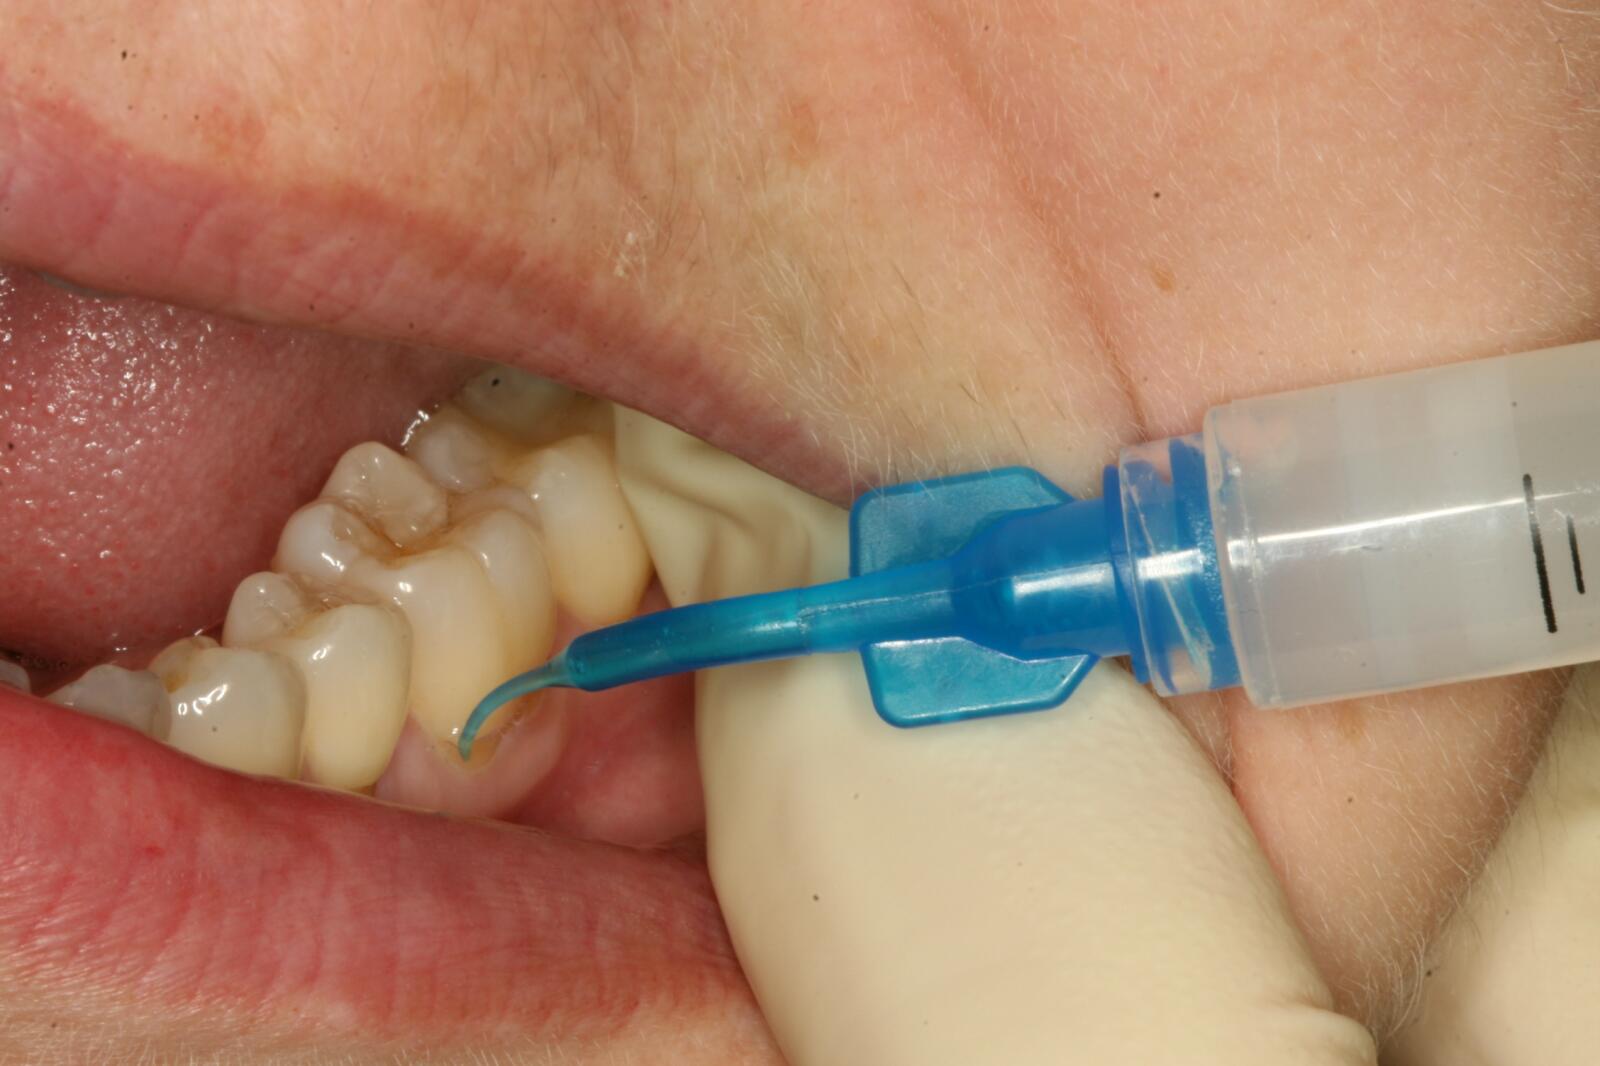

На фотографии метод лечения раннего кариеса – инфильтрация. При этом способе пораженный участок зуба безболезненно лечат химико-механической обработкой.

Способ инфильтрации был разработан в Германии. Метод характеризуется микроинвазивным лечением кариеса на стадии пятна. Процесс отличается лечением химико-механической обработкой, продолжительность которой составляет 15-20 минут. Отсутствие препарирования и болезненных ощущений — несомненные преимущества способа. Международные исследования доказали положительную динамику и полное устранение кариеса данным методом. Развитие кариозного пятна прекращается на любой стадии.